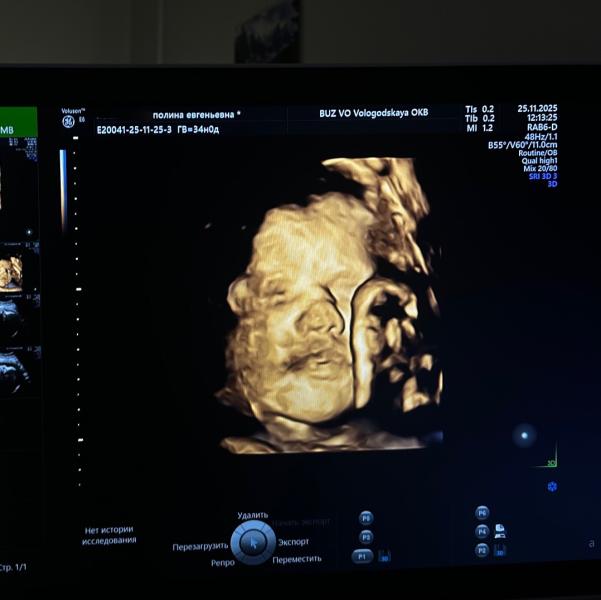

Доченька, это все благодаря твоему появлению в моей жизни! Своими активными пиночками ты даешь мне осознание реальности происходящего. Я люблю тебя больше жизни.

До нашей встречи осталось всего ничего. Мы с папой безумно сильно тебя ждём. Своим появлением в наших жизнях ты уже сделала нас самыми счастливыми людьми на планете! Спасибо тебе, наш маленький человечек❤️